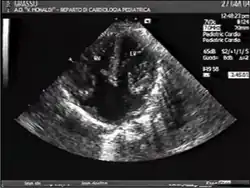

AVSDs can be detected by cardiac auscultation; they cause atypical murmurs and loud heart tones. Confirmation of findings from cardiac auscultation can be obtained with a cardiac ultrasound (echocardiography - less invasive) and cardiac catheterization (more invasive). It is also possible to diagnose AVSD in-utero via routine fetal ultrasounds or, more conclusively, fetal echocardiograms.[3]